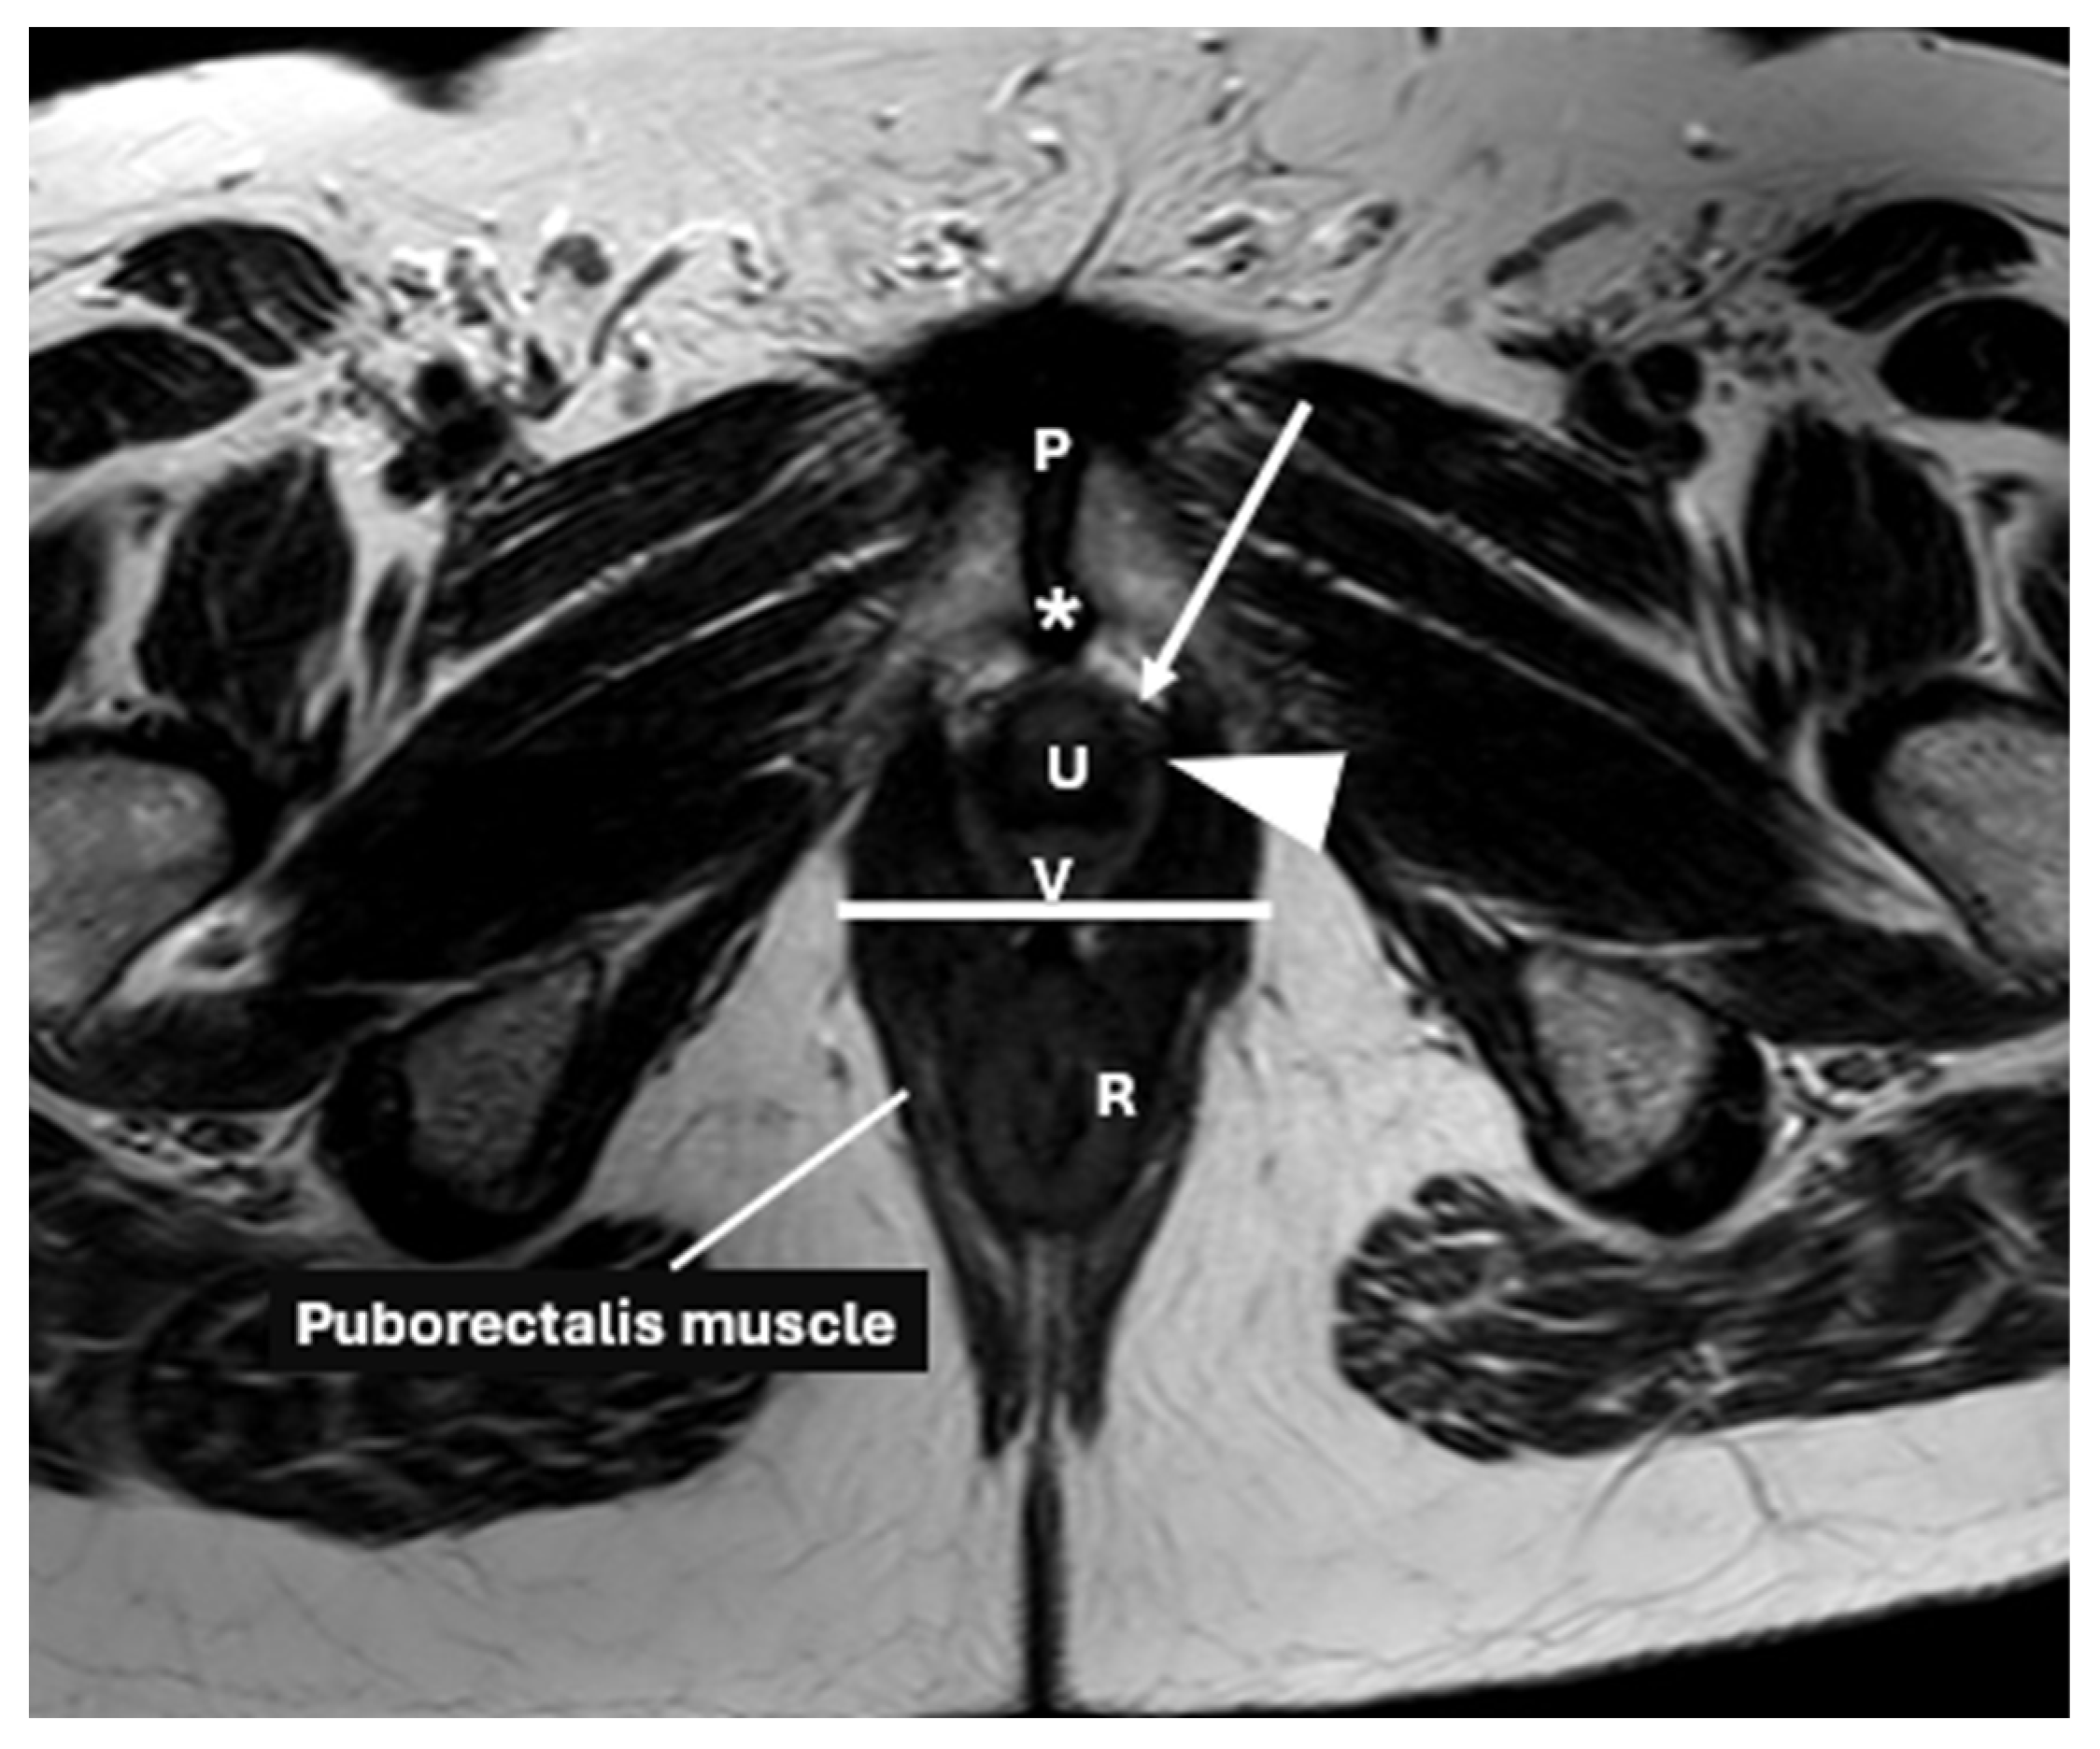

- Guo, M.; Zbar, A.P.; Wu, Y. Imaging the levator ani and the puborectalis muscle: Implications in understanding regional anatomy, physiology and pathology. Scand. J. Gastroenterol. 2023, 58, 1295–1308. [Google Scholar] [CrossRef] [PubMed]

| Anorectal Angle | Angle between the posterior distal rectum and the anal canal’s central axis | Reflects the levator ani muscle function during contraction | 108–127° at rest, decreases by 15–20° during contraction |